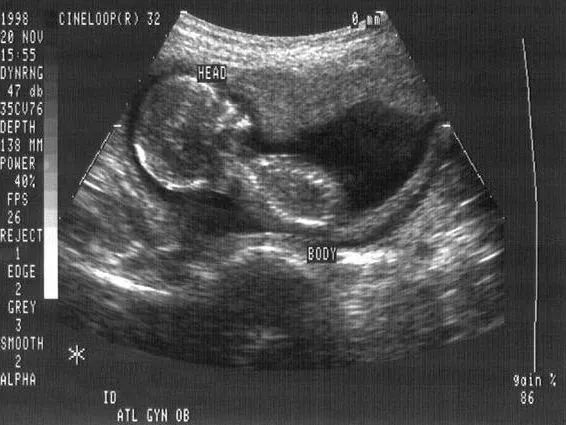

![]()

▲孕妇怀孕期间的B超图像